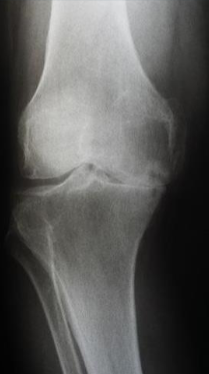

Osteoarthritis

Rheumatoid Arthritis

periarticular osteopenia

erosions

joint space narrowing